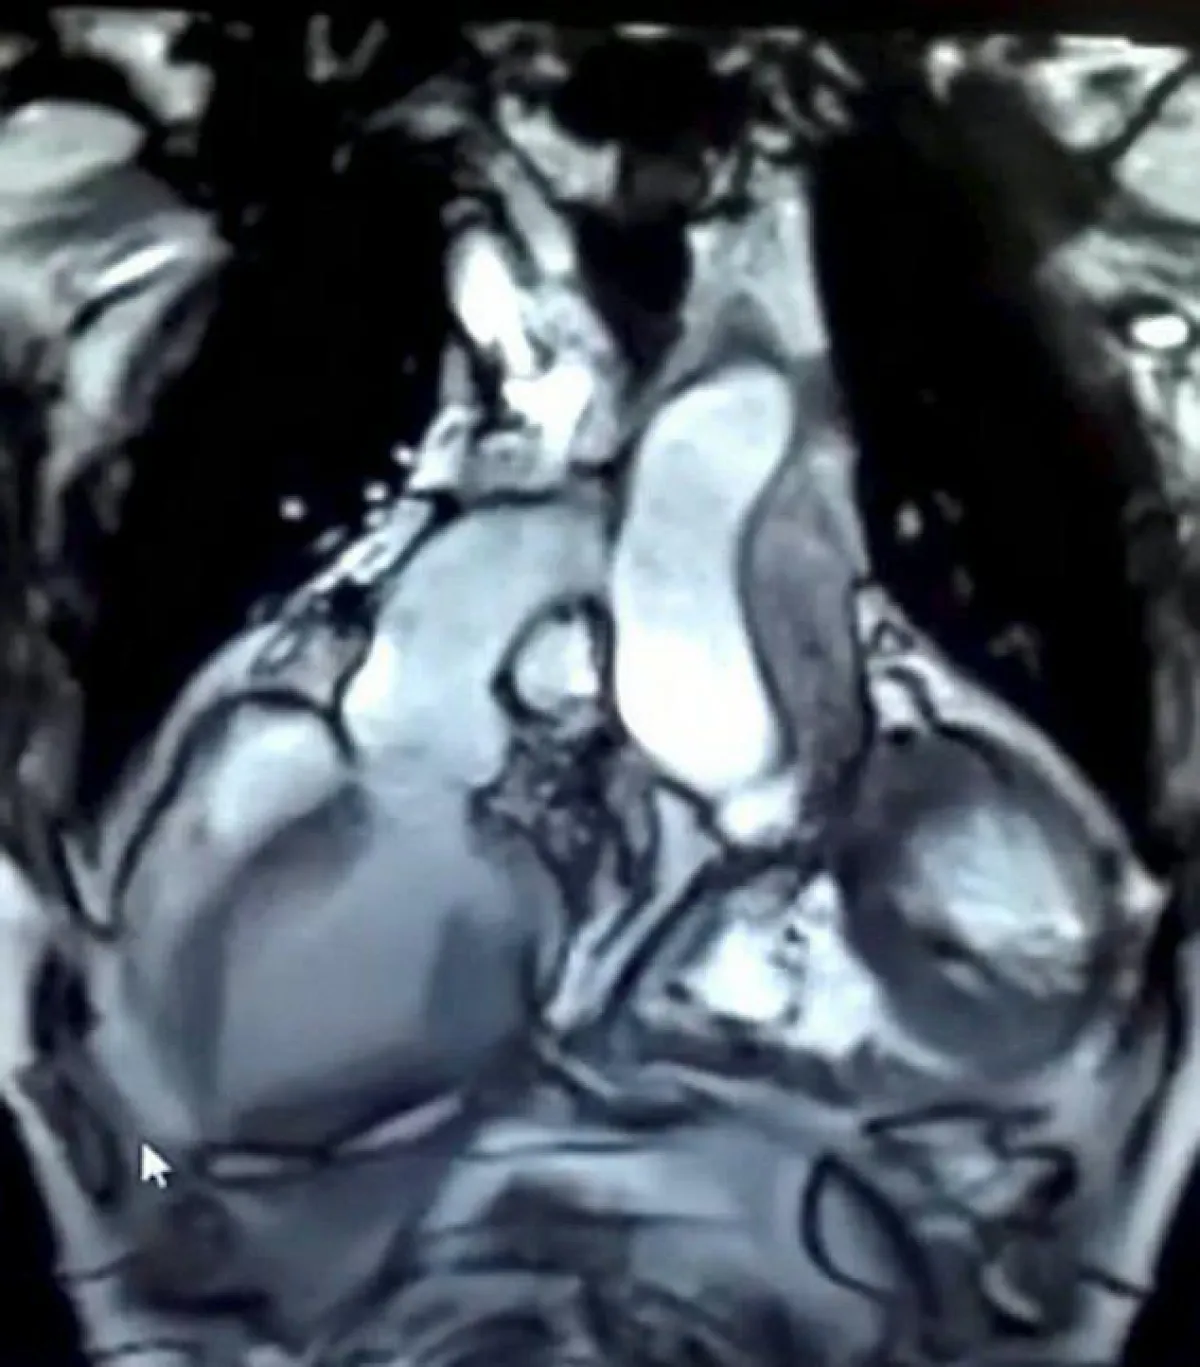

بسبب ذلك، قام الأطباء بزرع قلب صغير في تجويف صدر سوريش وربطه بالقلب القديم في عملية تعرف بزراعة القلب المنتبذ، حيث يملك سوريش قلبين الآن في عملية تعد الأولى من نوعها في آسيا والتي وصفها الأطباء بالصعبة، بعد أن تلقى سوريش القلب من متبرعة ولحسن حظه كان مناسب تماماً للتجويف بسبب صغر حجمه.